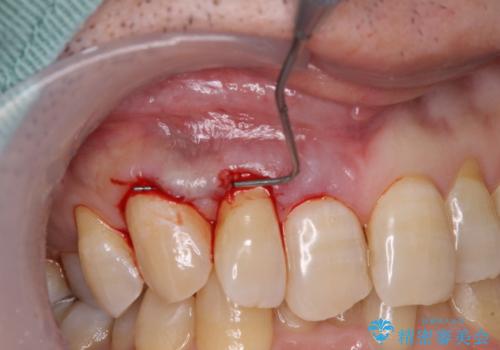

- 強い咬合力による歯肉退縮により、歯の根の黄色い色が見えてしまうことを気にされて来院された患者様です。

口蓋(上顎の内側)から採取した結合組織(歯肉の内側の組織)を移植することによる、根面被覆術を行うこととしました。

ディープバイトで咬合力が強く、該当歯に負担のかかりやすい咬み合わせであったため、歯肉退縮が起こりやすいと判断された患者様でした。

根面被覆を達成するとともに、歯肉の厚みを増すことで、今後歯肉退縮を起こしにくくするよう配慮した処置としました。